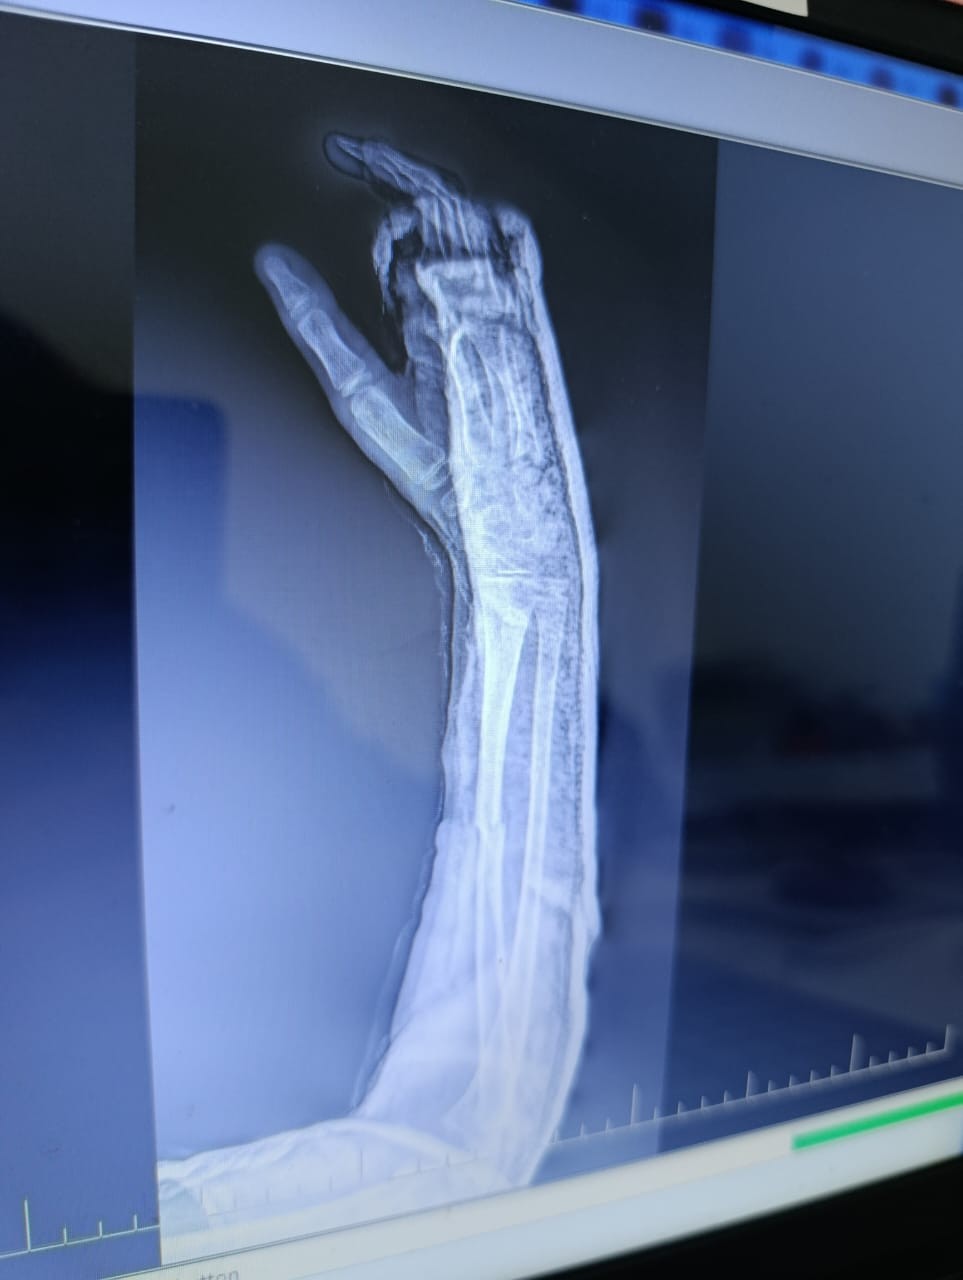

Здравствуйте, у сына, 10 лет, был перелом двух костей на правой руке. Одну кость вправили хорошо, другую на 50%. Врач говорит, что нет необходимости довправлять другую кость, но я переживаю и не понимаю как она может срастись. Сперва неделю ходил с лангетой, потом поставили гипс. Посмотрите пожалуйста снимки. Может ли кость нормально сростись или нужно настоять на операции, что бы вторую кость установили более ровно?